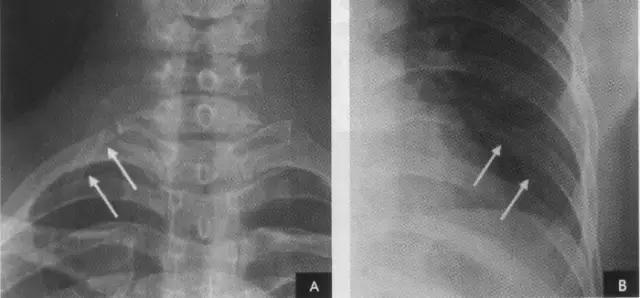

1、肋骨共12对,每根肋骨分为前肋、腋段和后肋三段:同一肋骨前后段的位置不同,一般第6前肋与第10后肋等高。前段扁薄,密度略低,自外上向内下倾斜走行并形成肋弓;后段圆厚,密度略高。呈水平状向外下走行;在无变异的情况下,两侧肋骨的位置及肋间隙的宽度基本对称,故肋骨及肋间隙常被用作胸部病变的定位标志。第1~10肋骨前端有肋软骨与胸骨连接,因肋软骨未钙化时不显影,故肋骨前端多呈游离状。25岁以后第1对肋软骨首先钙化,其他肋软骨随年龄增长,自下而上逐条钙化。第一肋骨常常显示不规则钙化区,尤其是中年以后。下部诸类也显示局限性的钙化,即使在成年人也是这样。在女性的软骨钙化常常示不规则的,造成斑点状形态。而在男性钙化可以局限于软骨之上下缘,造成线样阴影。有时下肋部肋软骨的钙化极为广泛,造成下肺野内带不规则的斑点状致密影。肋骨有很多种先天变异(下图),常见的有以下几种:

(1)颈肋自第7颈椎处发出,可发生于一侧或两侧,较第1对肋骨小,并往往较直而不呈弧形。有时第1对肋骨发育不完全,形态与颈肋相似,但根据第7颈椎的两侧横突向下倾斜,而第1胸椎的两贸横突向上倾斜的特征,可协助判断肋骨的起源:

(2)叉状肋为最常见的肋骨变异。多发生在第3、4肋骨,表现为肋骨前端呈叉状,亦可同时伴有增宽或缩短变形;或一支膨大另一支短小;或在肋骨上仅见一骨性突起;或在分叉的前端呈环状畸形。

(3)肋骨联合常见于第5、6肋骨后段近脊柱旁,相邻肋骨间有骨性联(又称骨桥),肋间隙变窄。

(4)肋骨缺如或发育不全。